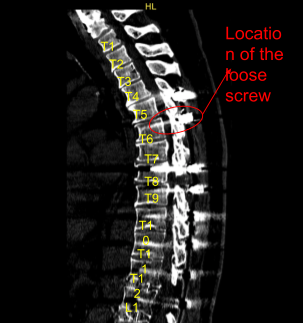

The physical examination showed tenderness of the paraspinal region at L5 on the left and right side. Fractured left-sided thoracic Z-rod with pseudoarthrosis and laterally placed proximal pedicle screw. Ct study conducted prior to the surgery supported the preoperative diagnosis of thoracic pseudoarthrosis.

Sagittal View of Preoperative CT-Scan